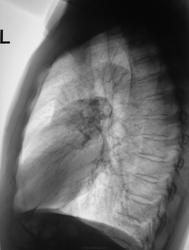

Надо бы исключать периферическую опухоль с параканкрозной пневмонией А это и есть первичный снимок? И томограммы есть?

Красивое, круглое, однородное, и на мой мой взгляд, бугристое. А меленькие интенсивные очаги - это сосудики. Я бы думала на онко

М\долевая косая плевра локально подтянута к образованию. Для пневмонии не характерно.

+1. Контуры местами нечеткие, местами бугристые, поэтому даже на инфицированную кисту мало похоже.

Да, динамика есть, относительно хорошая динамика. Кажется, что из корня лёгкого вылетела комента и упорно стремится к периферии, но вот "хвост" кометы, ну никак от тени корня оторватся не может...

Если присмотреться от этой тенюхе, то к корню тянется эдакая полосочка очень напоминающая дренирующий бронх;) Вполне может оказаться бронхогенной или энтерогенной кистой. Кстати, если далее были предоставлены снимки до лечения, а в начале темы выставлены снимки в динамике, то видно, что тень не гомогенная - может соответствовать нагноившейся кисте, а в дальнейшем произощло ее опорожнение через тот самый деренирующий бронх и стала видна стенка кисты с тоненькой полосочкой фиброза и тень стала содержать еще и воздух. Извиняюсь за каламбур)))

Предположу фокус шаровидной пневмонии… на фоне фиброза, пожалуй.